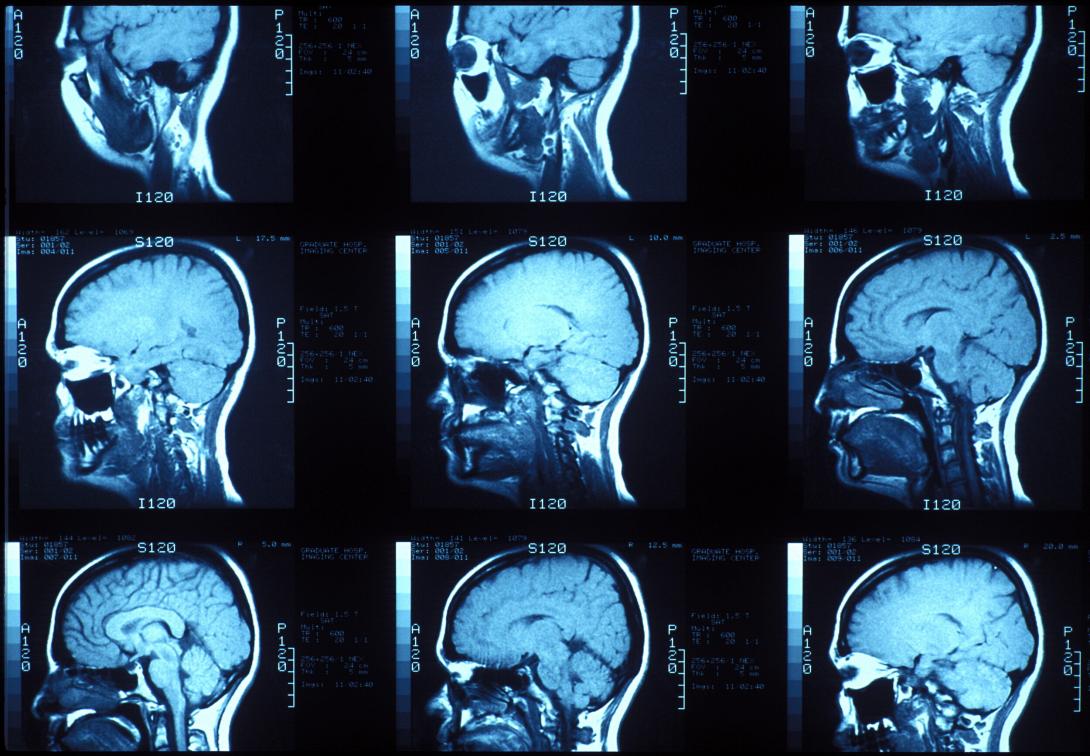

Oι εγκέφαλοι των ανθρώπων ήταν μεγαλύτεροι πριν από 3.000 χρόνια

Οι εγκέφαλοι των ανθρώπων ήταν μεγαλύτεροι πριν 3.000 χρόνια

Ο σύγχρονος πολιτισμός μας μπορεί να είναι ο πιο προηγμένος που υπήρξε ποτέ στη Γη, αλλά πριν από περίπου 100 γενιές, οι πρόγονοί μας είχαν εγκεφάλους μεγαλύτερους από τον δικό μας.

Πριν από αρκετές χιλιάδες χρόνια, οι άνθρωποι έφτασαν σε ένα ορόσημο στην ιστορία τους καθώς οι πρώτοι γνωστοί περίπλοκοι πολιτισμοί άρχισαν να εμφανίζονται. Ενώ, όμως, άρχισαν να φτιάχνουν τις πρώτες πόλεις και κοινωνικές δομές από τότε οι εγκέφαλοί μας αντί να έχουν μεγαλώσει όπως μπορεί να περίμενε κανείς, φαίνεται πως έχουν συρρικνωθεί ελαφρώς.

Ο χαμένος όγκος του εγκεφάλου, κατά μέσο όρο, είναι περίπου ισοδύναμος με τέσσερις μπάλες του πινγκ πονγκ, λέει ο Jeremy DeSilva, ανθρωπολόγος στο Dartmouth College στις ΗΠΑ. Σύμφωνα με μια ανάλυση κρανιακών απολιθωμάτων, την οποία δημοσίευσε ο ίδιος και οι συνεργάτες του πέρυσι, η συρρίκνωση του ανθρώπινου εγκεφάλου ξεκίνησε μόλις πριν από 3.000 χρόνια.